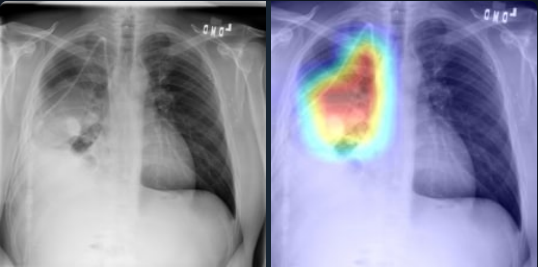

The Grad-CAM mappings of our 3-layer headed SwinCheX for samples containing Consolidation, Atelectasis, Mass or Cardiomegaly are provided in the Figure 3. Lung consolidation can be easily seen on an X-ray image by the naked eye. The consolidated parts of the lung look white, or opaque, on a chest X-ray. In Figure 3a our model detects these parts and diagnoses the sample as positive. Furthermore, an X-ray image can be helpful in the diagnosis of Atelectasis. Findings on an X-ray suggestive of Atelectasis include displacement of fissures, rib crowding, the elevation of the ipsilateral diaphragm, volume loss on ipsilateral hemithorax, hilar displacement, and compensatory hyperlucency of the remaining lobes. In Figure 3b, our model has diagnosed this disease by looking at the bottom of the two lungs and their relative positions.

Refer to caption

(b) Atelectasis

Figure 3: Grad-CAM of our model for positive samples containing Consolidation, Atelectasis, Mass, or Cardiomegaly. For each sample, the original image is shown on the left and the Grad-CAM of the 3-layer headed SwinCheX is shown on the right.